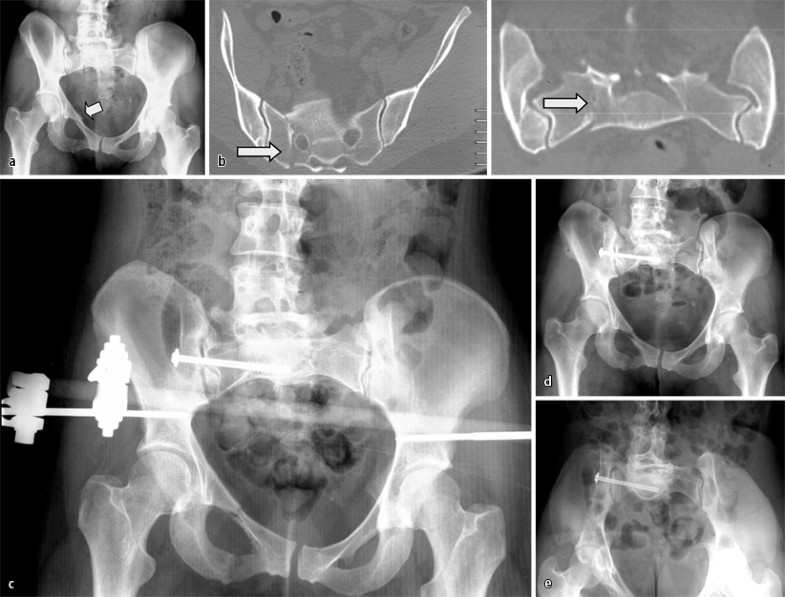

Neben der klinischen Untersuchung ist die konventionelle Röntgenbilddiagnostik die Standardbildgebung (Ausgangsbild) und bleibt dies vorläufig auch. Auch in der Zeit der vielzeiligen Spiral-CT mit multiplanarer Rekonstruktion erscheint das a.-p. Röntgenbild des Beckens bis auf weiteres unverzichtbar zur Erstbeurteilung [13]. Insbesondere, wenn eine umgehende Indikation zur CT gestellt wird, wird die nahe Zukunft zeigen, inwieweit die typischen Standardserien (a.-p. plus Ala- und Obturatoraufnahme bei der Azetabulumfraktur, a.-p. plus Inlet- und Outlet-Aufnahme bei Beckenringverletzungen; Fall 1, Abb. 1, Fall 2, Abb. 2) durch die entsprechenden CT-Rekonstruktionen ersetzt werden können (Fall 2, Abb. 2). Volumenorientierte 3D-Rekonstruktionen bieten eindrückliches Bildmaterial, können bei geringer Dislokation der Frakturen aber die Frakturerkennung erschweren [22]; zur Bewertung der eigentlichen Pfannenregion ist bei Azetabulumfrakturen das „Herausrechnen“ des Femurkopfs nötig.

Die Standardbilddiagnostik bildet derzeit noch die Grundlage der Frakturklassifikation [13]. Wird das primäre Standardröntgenbild, das etwa zum Frakturausschluss angefertigt wird, fehlinterpretiert, resultiert oft auch eine therapeutische Fehlentscheidung (Fall 1, Abb. 1).

Fall 1, 32-jährige Patientin, AO-Fraktur 61B2.1., a a.-p. Beckenübersichtsaufnahme, b CT: Kompressionsfraktur der rechtsseitigen Massa lateralis, c a.-p. Beckenübersichtsaufnahme postoperativ, d,e Beckenübersichts- und Inlet-Aufnahme nach Entfernung des Fixateurs und Vollmobilisation, weitere Erläuterungen s. Kasuistik

Die 32-jährige Patientin war im europäischen Ausland gestürzt und nach Vorlage der a.-p. Beckenübersichtsaufnahme (Abb. 1 a) mit „stabiler“ isolierter vorderer Beckenringfraktur unter starken Beschwerden voll mobilisiert worden. Die rechtsseitige Sakrumfraktur wurde erst 10 Tage nach dem Trauma und der Rückkehr in die Heimat diagnostiziert (Abb. 1 b).

Die Fraktur wurde reponiert und mittels supraazetabulärem Fixateur externe und transiliosakraler Stellschraube stabilisiert (Abb. 1 c). In Abb. 1 d,e sind die Beckenübersichts- und Inlet-Aufnahme nach Entfernung des Fixateurs und Vollmobilisation dargestellt.